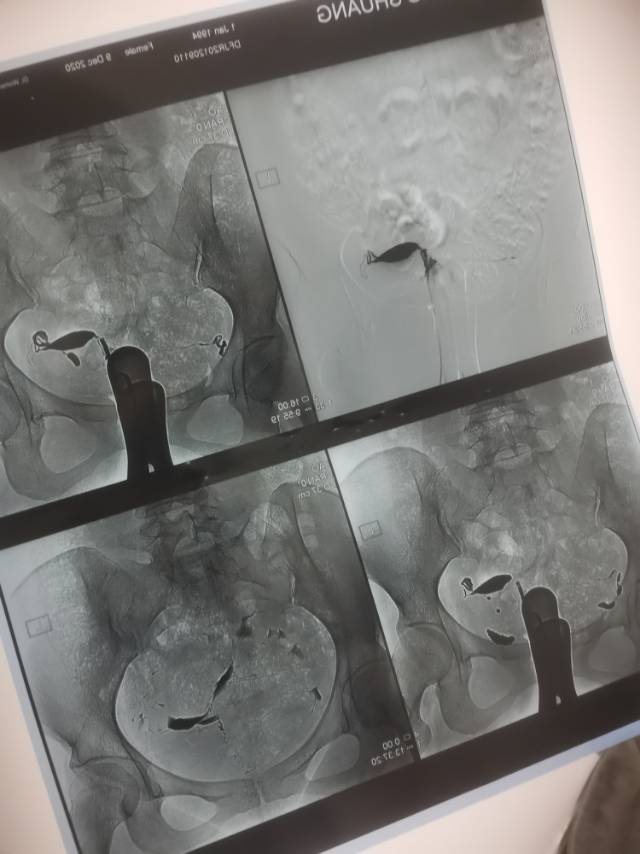

备孕一年多一直没有消息,前几天做了输卵管造影,显示双侧通畅,本来特别开心,但是后来拿给医生看片子,说我有一侧输卵管位置不正,基本上不能受孕。这种情况应该怎么办呢?

1.男方精液查了吗?正常不正常? 2.如果男方精液还可以,可以监测排卵,我看有一侧输卵管还可以,可以监测这侧排卵时试孕 2.如果监测3个月左右还没怀孕,可以试试人工授精,实在不行,可以做试管助孕的,总是有办法的

你的输卵管位置没那么漂亮只是怀孕概率降低,不是完全不能怀。所以你可以一边卵泡检测一边试试自然怀孕。